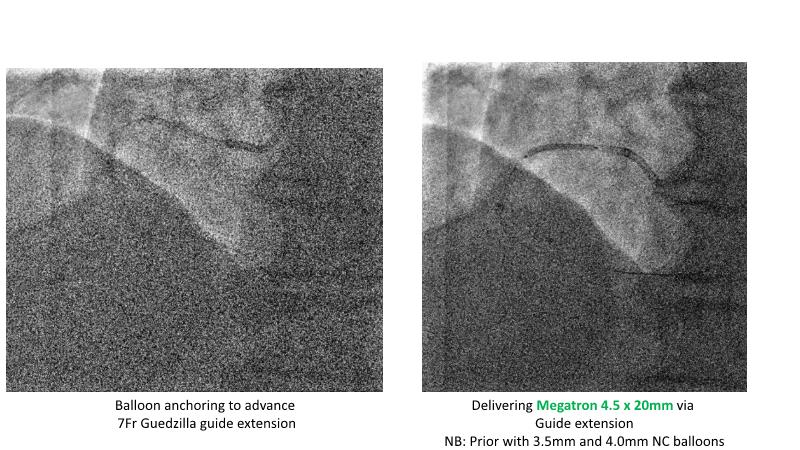

This session is recommended for you if you are seeking insights into the advantages of using IVUS imaging over visual assessment for better outcomes in left main bifurcation procedures. Discuss with experts the benefits of using RotaCUT in lesion preparation for left main bifurcation and explore the impact of high radial strength stents on the procedure's success.

• To see advantages of RotaCUT as part of lesion preparation in left main bifurcation

• To know how a high radial strength stent can make a difference in left main bifurcation